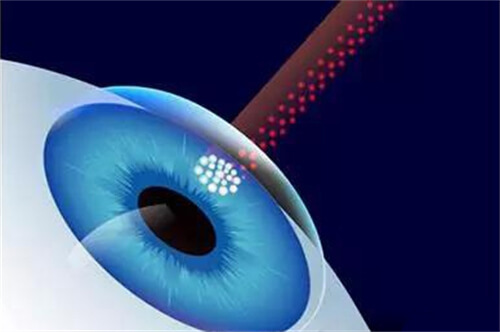

对于黄斑病变患者,她能熟练进行抗VEGF药物注射治疗,有效控制病情发展。

实例二:42岁女性糖尿病患者,因"双眼视力逐渐下降"就诊。检查发现双眼严峻的糖尿病视网膜病变伴黄斑水肿。雷医生为其制定了系统的治疗方案,包括视网膜激光治疗和抗VEGF药物玻璃体腔注射。经过6个月治疗,患者视力稳定,黄斑水肿明显减轻。

眼内注药术:治疗黄斑水肿、新生血管等